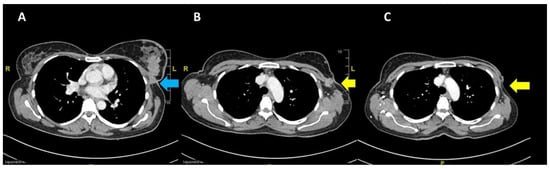

The patient was started on tamoxifen therapy for the breast cancer. A CT scan at 2 months post-op showed no local recurrence of the left breast carcinoma nor contralateral involvement, and showed resolution of the lung metastasis (Figure 4). However, the cervical carcinoma size increased with adjacent inflammatory changes, consistent with progressive disease (Figure 5A). No pelvic lymphadenopathy and no distant metastases in the abdomen were noted. The patient then completed CCRT consisting of 25 fractions of external beam radiation and weekly cisplatin 40 mg/m2, with additional 8 fractions of external beam radiation as booster. The size of the cervix was consequently reduced (Figure 5B); no tumour mass was noted on the cervix and vagina. In addition, no malignant cells were observed in the cervical smear.

Figure 4. Pre-chemotherapy CT scan showing (A) the primary breast lesion (blue arrow) and (B) the level of arch of the aorta (yellow arrow indicates fixed nodes to the pectoral muscle laterally); (C) post mastectomy at 2 months showing no local recurrence at the left breast.